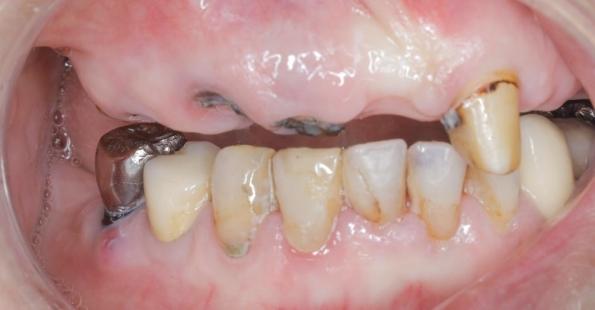

全口牙缺失的選擇

三、缺牙對咬合的影響

對鄰牙的影響

缺牙后,鄰牙會向缺牙間隙傾斜,對頜牙會伸長,從而導致咬合關(guān)系紊亂。長期以往,會增加鄰牙齲壞、牙周病的發(fā)生風險。